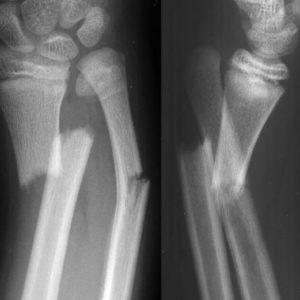

Перелом голени встречается в 20% случаев и не зависит от возраста человека. Диагностику переломов проводит врач-травматолог с помощью пункции и рентгена. Внутрисуставные переломы голени требуют проведения магнитно-резонансной или компьютерной томографии.

Травматолог произведет осмотр, сделает рентген и соберет анамнез, оценит подвижность суставов, проверит кровоснабжение и чувствительность тканей.